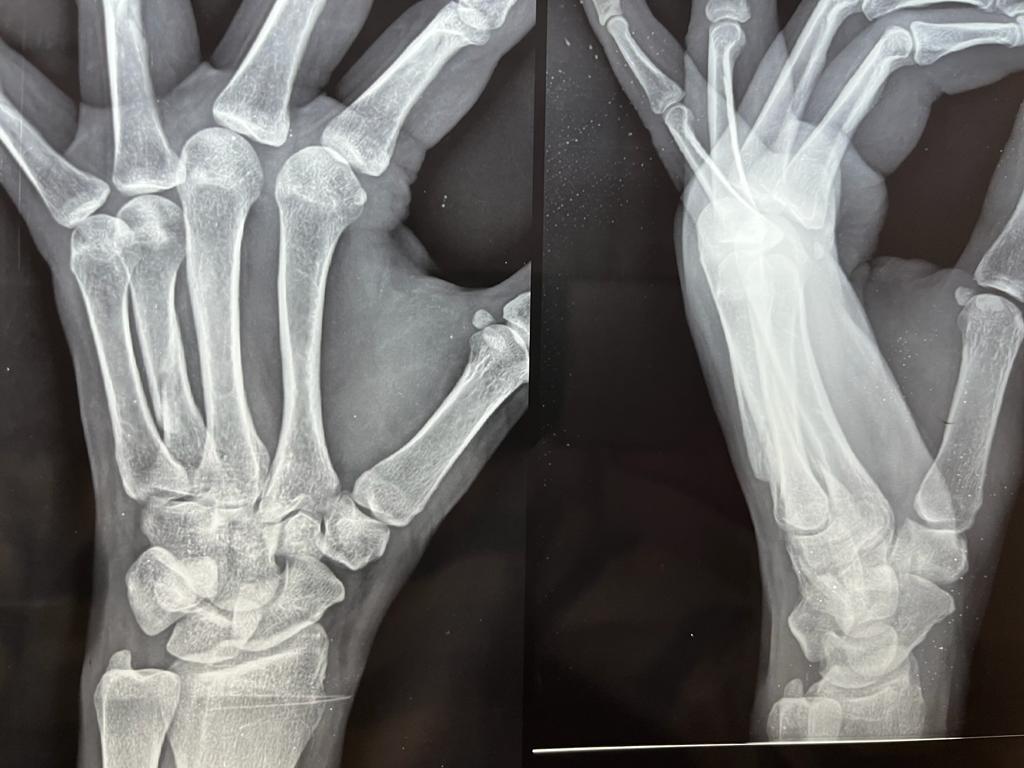

Old transscaphoid perilunar dislocation,proximal Instead of row Carpectomy done